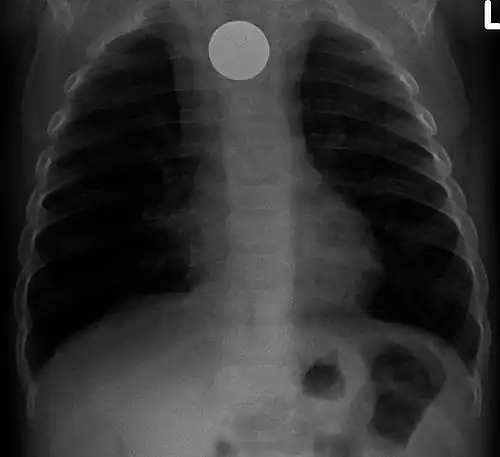

AP X ray showing a 9mm battery in the intestines -

Lateral X ray showing a 9mm battery in the intestines -

Multiple button batteries in the stomach -

Button battery in the stomach